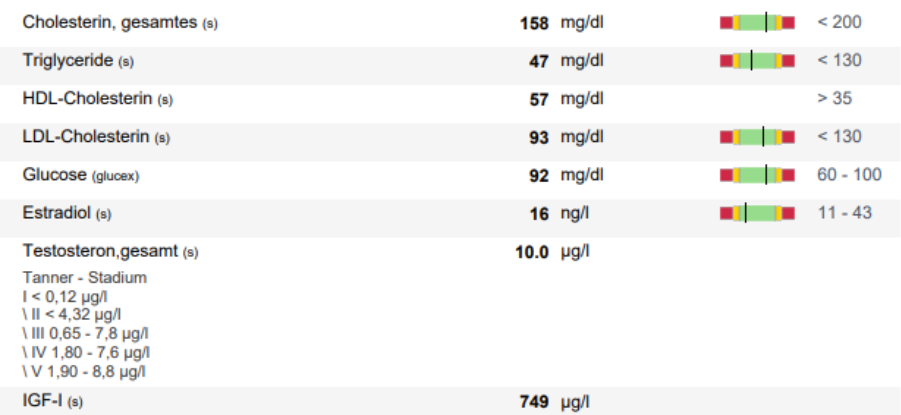

on 22nd of august, so ten days after starting exemestane I got another blood test done where i checked:

-Estradiol

-IGF-1

-Lipids (cholesterol & triglycerides)

-Total Testosterone

-Glucose

The results honestly couldn’t have been much better.

perfect Estradiol and almost too much IGF-1